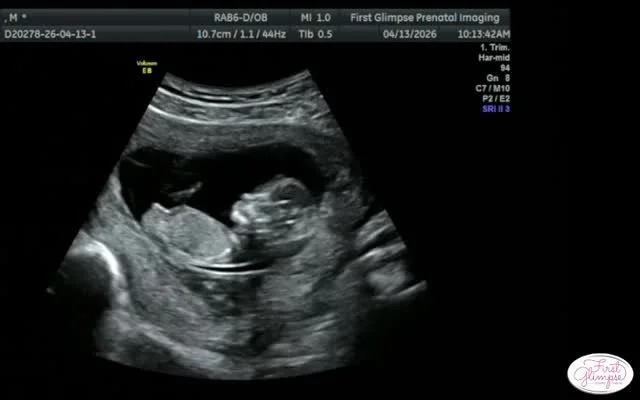

Ultrasound Packages

A WARM & INVITING ENVIRONMENT TO CREATE MEMORIES

that will last a lifetime.